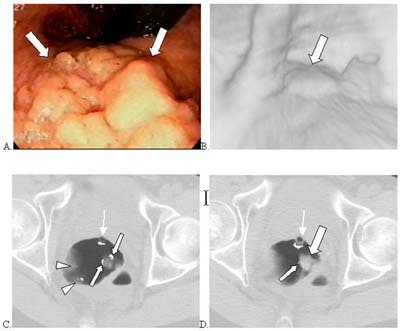

![]() |

| Above, 8-mm polyp in the sigmoid colon detected by CAD. Left: axial image showing the polyp (arrow). Right: Endoscopic view of the polyp. Green indicates a region identified by CAD as a polyp. Image courtesy of Dr. Hiro Yoshida. |

| Ten-millimeter polyp in the hepatic flexure detected by CAD. Left: axial image showing the polyp (arrow). Right: Endoscopic view of the polyp. Green indicates a region identified by CAD as a polyp. Image courtesy of Dr. Hiro Yoshida. |

"In summary, the CAD based on geometric and texture features showed a potential to detect polyps with high sensitivity and a low false-positive rate," Yoshida said. "Potential benefits are reduced interpretation time and improved diagnostic performance."